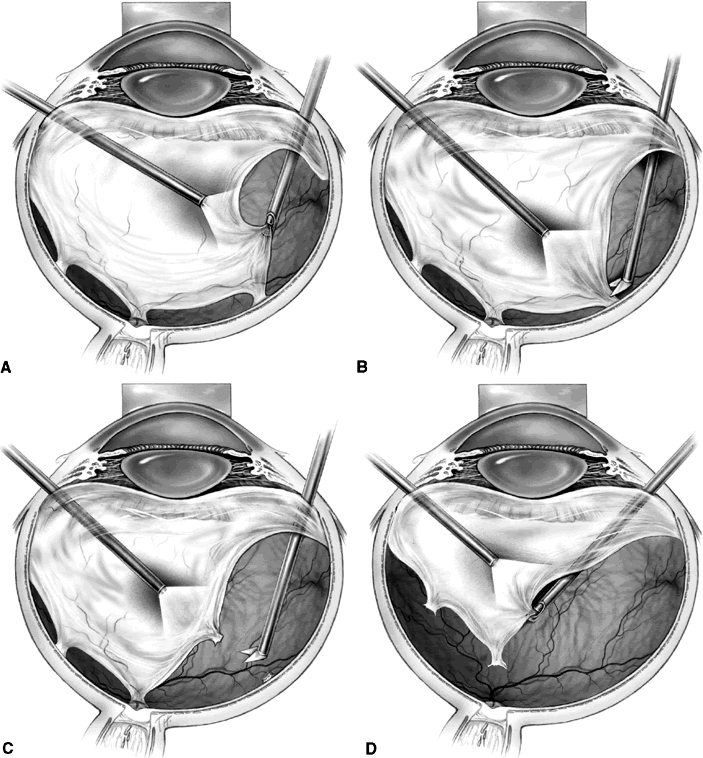

Segmentation was the earliest method used to release retinal traction caused by preretinal fibrovascular proliferation. A core vitrectomy is first performed (Fig. 1A). Anteroposterior traction then is released by circumferentially cutting the posterior vitreous surface around the area of epiretinal proliferation (see Fig. 1B). After the anteroposterior traction has been released and the formed vitreous has been removed, the posterior vitreous surface is cut between epicenters of fibrovascular adhesion, leaving islands of fibrovascular tissue. It also may be necessary to excise bridges of fibrovascular tissue connecting epicenters, using the vitrectomy probe or intraocular scissors (see Fig. 1C). Bleeding often is a problem during segmentation because the neovascular tissue is cut far away from its origin within the retina. Intraocular diathermy often is required to control bleeding from stumps of severed fibrovascular membranes. Raising the intraocular pressure also can be used temporarily to control intraoperative hemorrhage. Finally, panretinal endophotocoagulation is applied (see Fig. 1D).

Fig. 1. A. Core vitrectomy is performed. B. Peripheral vitreous is removed, releasing all anteroposterior traction on the epiretinal membrane. C. The epiretinal membrane is segmented by cutting bridging tissue between foci of fibrovascular adhesion. D. Segmentation has been completed, and panretinal endophotocoagulation is applied.